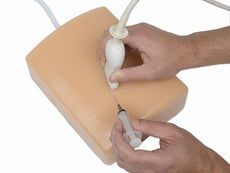

Bone Fracture Ultrasound Training Block, Crepitus Fracture

These bone-fracture training blocks help learners develop and practice the psychomotor skills necessary to gain ultrasound proficiency, including using ultrasound system controls, positioning and moving the transducer, recognizing bone fractures and manipulating fractured bones to identify normal versus abnormal imaging characteristics. Choose from two options: Greenstick Fracture, or Crepitus Fracture.

RESPECTIVE ANATOMY:Crepitus Bone Fracture

Greenstick Bone Fracture

DIMENSIONS:

Size: 7" long x 5" wide x 2.5" high (17 cm long x 13 cm wide x 6 cm high)

Weight: 3 lbs. (1.3 kg)